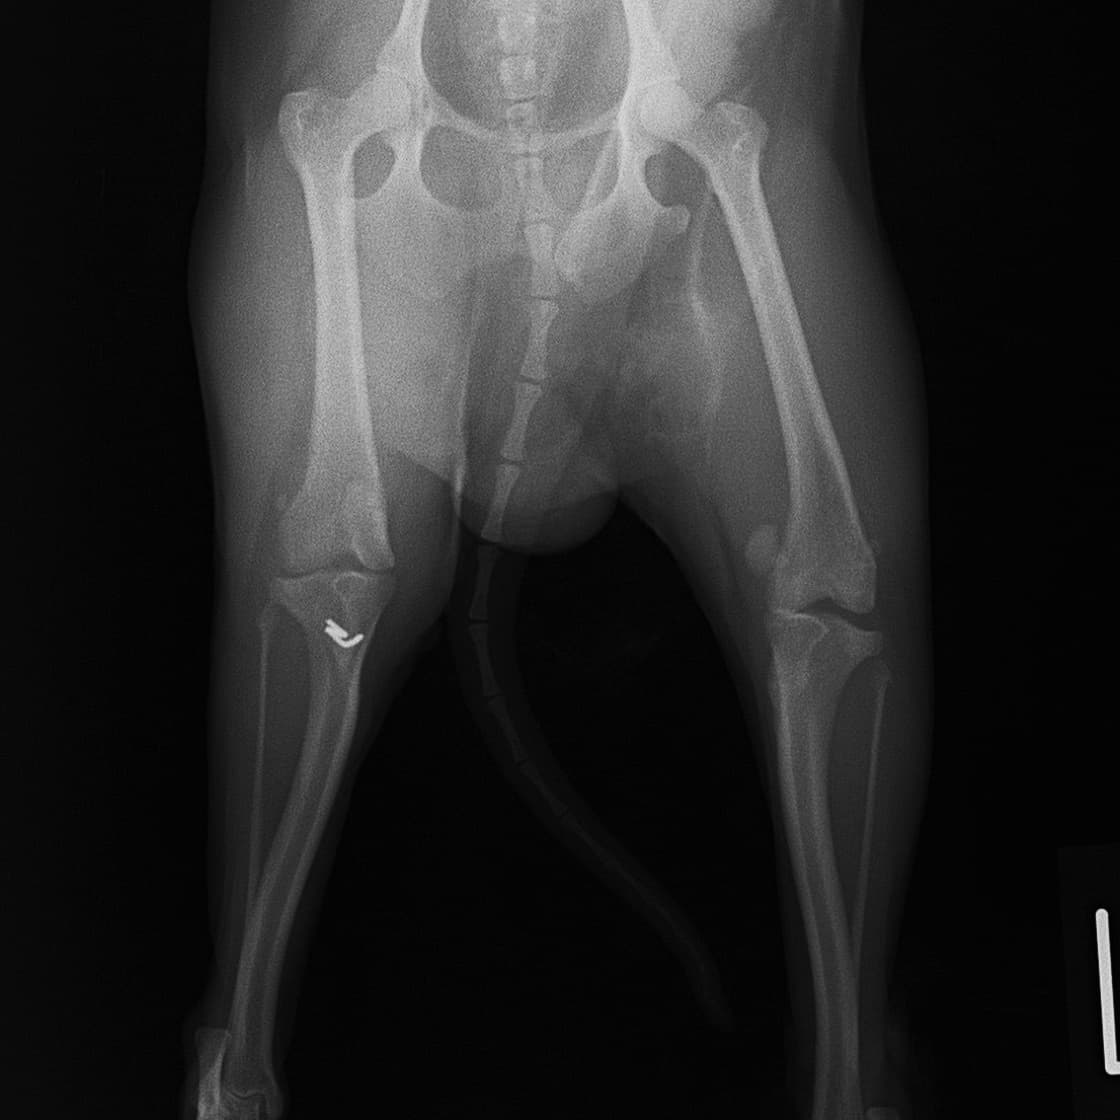

■ 症例20 ポメラニアン 8ヶ月 1.8kg

左右膝蓋骨脱臼 グレードⅢ

2ヶ月前から間欠的跛行が認められ、両膝の膝蓋骨脱臼整復術を行った。

手技は縫工筋及び内側広筋の解放、脛骨粗面の外側転位、滑車ブロック形造溝術、内外側関節包の縫縮を選択し実施した。

右側の膝蓋骨脱臼は上記手技で整復されたものの、左側はそれのみでは膝蓋骨が浮く様子が認められた。その為、PDS縫合糸にて膝蓋靱帯を1糸のみ縫合し、靱帯の縫縮を行った。

膝蓋骨脱臼は膝関節における膝蓋骨の内外側の脱臼と定義されるが、時として単純な内外の脱臼ではなく、膝蓋骨が大きく前方に浮き上がるように脱臼する場合がある。特にトイプードルやポメラニアンといった犬種に多く認められる。

内側脱臼に加えて前方への浮き上がりを矯正する為に、従来より脛骨粗面転移により膝蓋靭帯を外方と下方に引っ張り、固定する方法を選択する。膝蓋骨の前方への浮き上がりが軽度の場合は、従来法ではなく関節包の縫縮で対応していた。しかし、一部の症例で膝蓋骨の動きが悪くなり伸展機構が円滑に機能せずロボット様歩行になるケースがあった。

その為、膝蓋靭帯自体を縫縮する方法を採用した。この方法により、膝関節の伸展機構を妨げず膝蓋骨の軽度の浮きを矯正することが可能となった。

本症例の経過は良好である